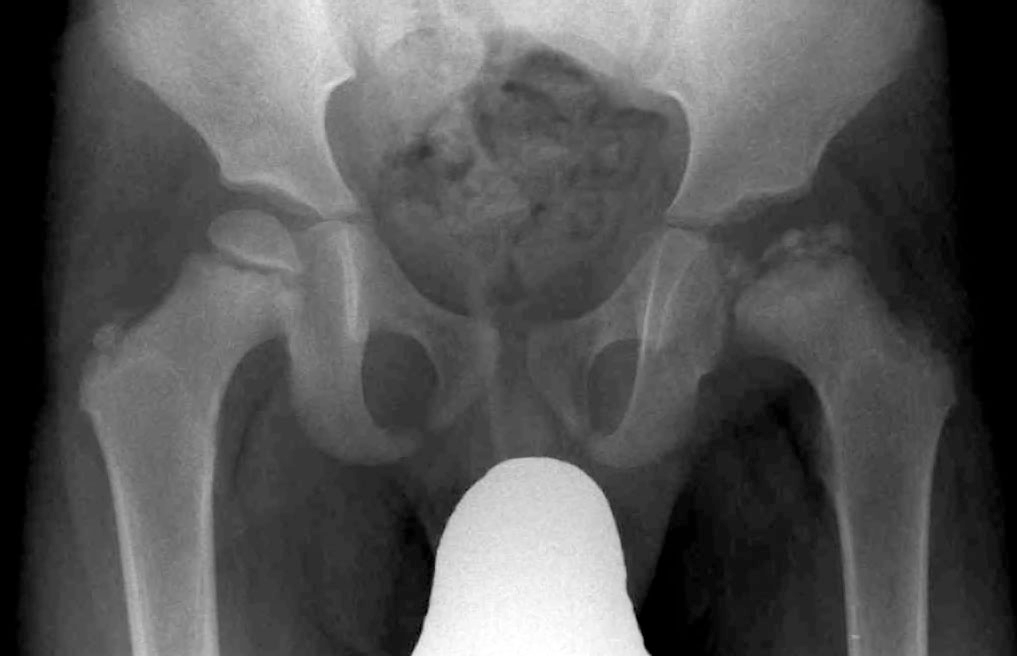

How does the proximal femur look in anatomic position

Femoral necks partially foreshortened

Lesser trochanters partially visible

How does the proximal femur look in internal rotation?

Toes in, heels out

Lesser trochanters not/barely visible, greater trochanters in profile

How does the proximal femur look in external rotation?

Femoral neck greatly foreshortened

Lesser trochanters visible internally

Exposure techniques for hips/pelvis

kVp - 77 to 85

Grid needed

40” SID

Cross-table hip varies with kVp

In a LPO, how do the hips and obturator foramen appear?

Left hip elongated, right obturator foramen open (criss-cross)

In a RPO, how do the hips and obturator foramen appear?

Right hip elongated, left obturator foramen open (criss-cross)

What are some ways to find CR for an AP hip?

Imaginary T between ASIS and pubic symphysis

Ken doll crease

Lines up with wrist when arms next to side

Where should the top of the IR be for an AP hip?

ASIS (do not include top of ilium)

What are the different views used for the hips and pelvis?

1-view pelvis = full pelvis shot

2-view hip = full pelvis, and single lateral of affected side OR single AP hip with single lateral on affected side

Collimation for hip x-ray

10×12 normally, but with prosthetic full 14×17

How to differ between a pubic inlet x-ray vs outlet

Inlet - Looks like a balloon (caudal angle)

Outlet - Looks like a butterfly (cephalic angle)

How to hang a cross-table hip x-ray?

Entire acetabulum must be visible, lay image so butt is down and pubic symphysis is up